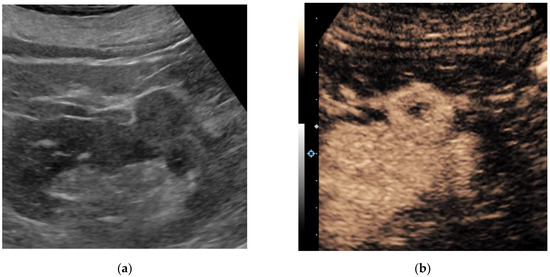

3.1. Contrast-Enhanced Ultrasound